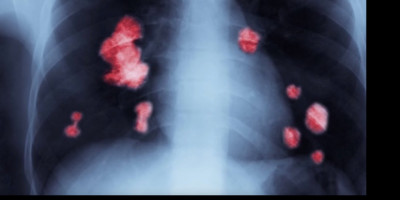

U Velikoj Britaniji, doktori i naučnici su stvorili model veštačke inteligencije koji može da identifikuje rak u ranim fazama. Ovo može ubrzati dijagnozu i lečenje pacijenata, piše Gardijan.

Alat za veštačku inteligenciju razvili su stručnjaci iz Roial Marsden NHS fondacije, Instituta za istraživanje raka London i Imperial College London. Može da utvrdi da li su abnormalni rastovi pronađeni na CT skeniranju maligni.

Tim je koristio CT skeniranje oko 500 pacijenata sa velikim plućnim čvorovima da bi razvio algoritam veštačke inteligencije. Ova tehnika može izvući vitalne informacije iz medicinskih slika koje je ljudsko oko teško videti.

Prema početnim rezultatima, čini se da AI model tačno identifikuje kancerozne velike čvorove u plućima.